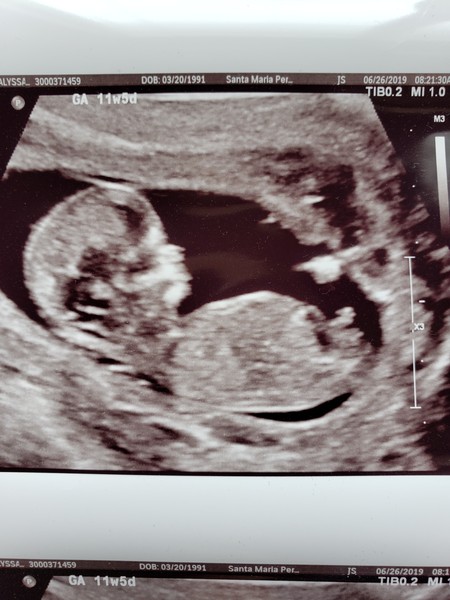

Lyssa91 · 06/08/2019 05:09

Anybody familiar with the nub theory and want to take a guess at my babies gender? Just for fun!